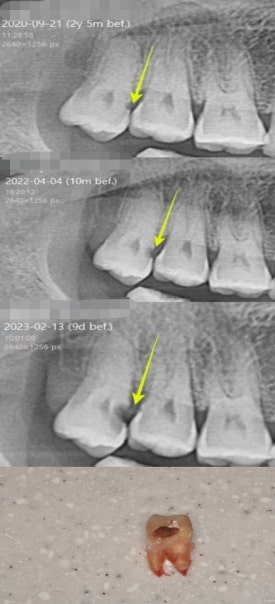

1. 사랑니에 생긴 충치 제때 발치하지 않아서 결국 엄청난 통증으로 치과에 내원하여 발치했던 케이스

사랑니 쪽에 충치가 생겨있으니 나중에 아파지기 전에 빨리 빼는 게 좋아요. 라고 말씀드렸던 두 분입니다.

”지금 별로 안 아프기 때문에 안 뺄래요”라고 하셨다가 수년 뒤, 너무 아파서 잠도 못 잤다고 하면서 치과에 내원하셔서 발치를 했습니다.